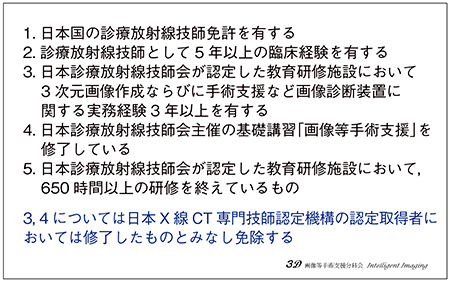

そこで,2016年に日本診療放射線技師会(JART)の分科会として“画像等手術支援分科会”が発足し,「画像等手術支援(Intelligent imaging)認定診療放射線技師」認定制度が始まりました。委員長は横町さんの元上司である石風呂 実先生(現・東京健康科学大学ベトナム)で,私と平野さんも委員を務めています。分科会の名称は診療報酬の「画像等手術支援加算」からですが,手術支援のための3D画像に限定せず,3D作成など画像処理全般に関する育成事業や認定を行っています。認定試験の受験資格は図1のとおりですが,残念ながらコロナ禍の影響で2019年度の第2回認定試験以降,開催できておりません。

図1 日本診療放射線技師会「画像等手術支援(Intelligent imaging)認定診療放射線技師」の受験資格

平野*:受験資格にある“650時間以上の研修”は,当面の期間免除になりますので,手術支援画像や3D作成に興味のある方は,どんどん受験してほしいです。認定施設は少し先の話となりますが,専門の教育が行える認定指導者の制度が動いていますので,各地域での普及にも取り組んでいただければと思いますね。